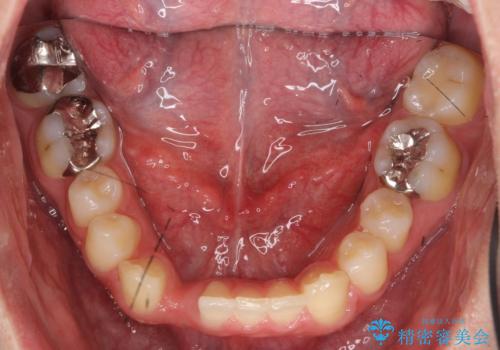

- 下の前歯が1本生まれつき少なかったため、インプラント治療を行いました。

インプラントの前に矯正治療を行い、入れる隙間を確保しました。

ブリッジにすることも可能でしたが、両側の歯が天然歯であること、また、事前に矯正で噛み合わせを整え、幅も確保していたこと、CTにより骨の厚みがある程度あったことを踏まえ、インプラントも可能であるとお話しし、選んでいただきました。